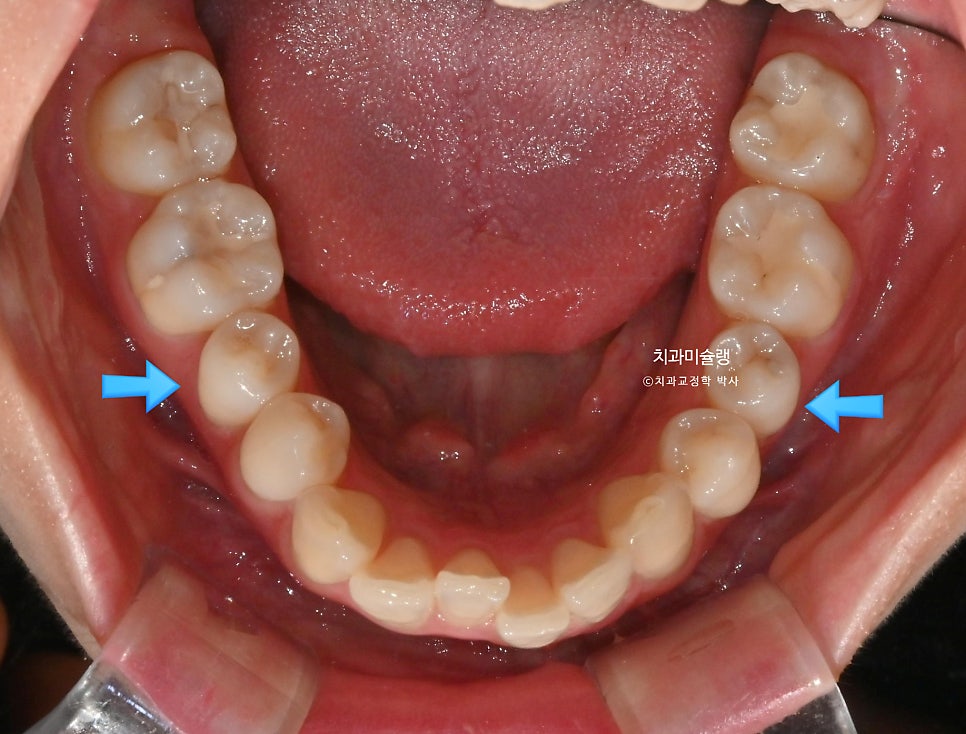

하악소구치 회전의 기술적 어려움

인비절라인 교정에서 투명장치만으로 가장 어려운 치아이동은 바로 <하악소구치의 회전> 입니다.

환자가 아무리 열심히 껴도 어태치먼트 한두개로는 택도 없는

치아이동이기에, 하악 소구치 회전이 요구되는 경우는 부가장치를 붙여서 해결해야 합니다.

여기 저기 붙어있는 금속 고리의 정체는 좀전에 언급한 작은어금니 회전을 위한 부가장치 입니다.

이 부가장치에 고무체인을 걸어놓음으로써 소구치의 회전이 첫세트에서 완료되었는데

4개월간의 회전 개선량을 표시해보면 이러합니다.

작은어금니 회전까지 완벽 개선되었습니다.